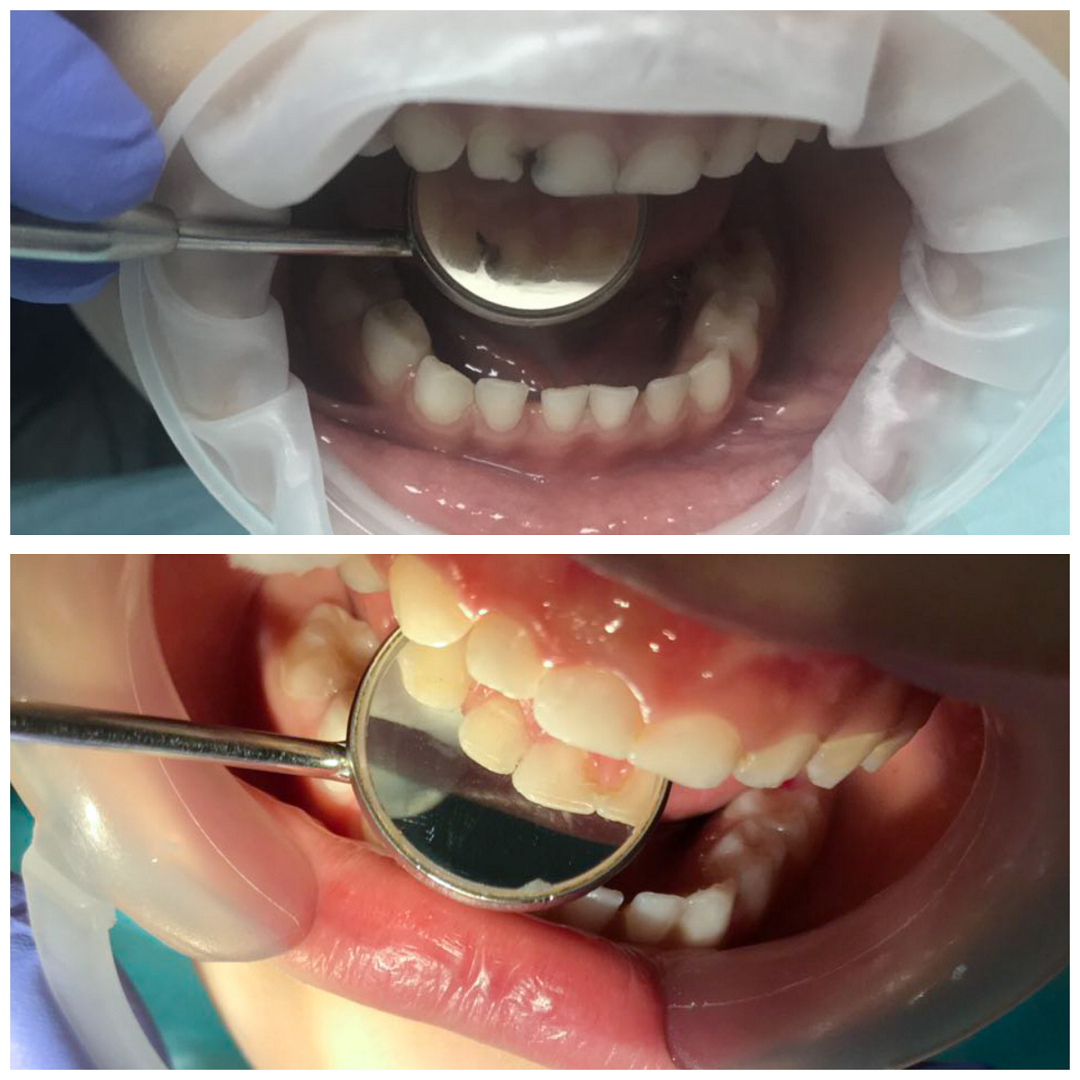

фото: Егана Маруфиди

есть такое заболевание - портальная гипертензия (синдром повышенного давления в системе воротной вены, вызванной нарушением кровотоков в портальных сосудах, почечных венах и нижней полой вене). Скажу проще. Диагноз сложный. Благодаря внимательной и ответственной маме девочка с портальной гипертензией наблюдается с 2,5 лет. И вот уже почти 3 года родители и врачи-стоматологи борются за сохранение зубов. Основная задача стоит в том, чтобы максимально сберечь оставшиеся зубы, для сохранения правильного прикуса у девочки.

Как видите, на состояние зубов ребенка могут влиять не только слабая эмаль или плохая гигиена полости рта, но и заболевания. Грамотный стоматолог по состоянию зубов может выявить серьезное заболевание в организме еще до появления основных симптомов и предложить пройти обследование у врачей. Но чаще, уже основной специалист во время лечения направляет ребенка к стоматологу для спасения и сохранения оставшихся зубов